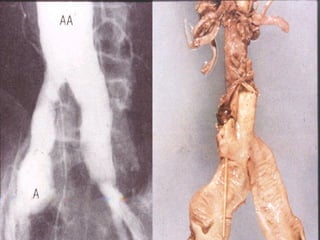

Daño a Órgano Blanco: Corazón:  Hipertensión maligna SNC:  Encefalopatía hipertensiva, Hemorragia cerebral, Infarto cerebral, Isquemia C. Transitoria Riñón:  Nefroesclerosis, Insuficiencia Renal Vasos:  Aneurismas, Disección aórtica

Daño a ÓrganoBlanco: Corazón: Hipertensión maligna SNC: Encefalopatía hipertensiva, Hemorragia cerebral, Infarto cerebral, Isquemia C. Transitoria Riñón: Nefroesclerosis, Insuficiencia Renal Vasos: Aneurismas, Disección aórtica